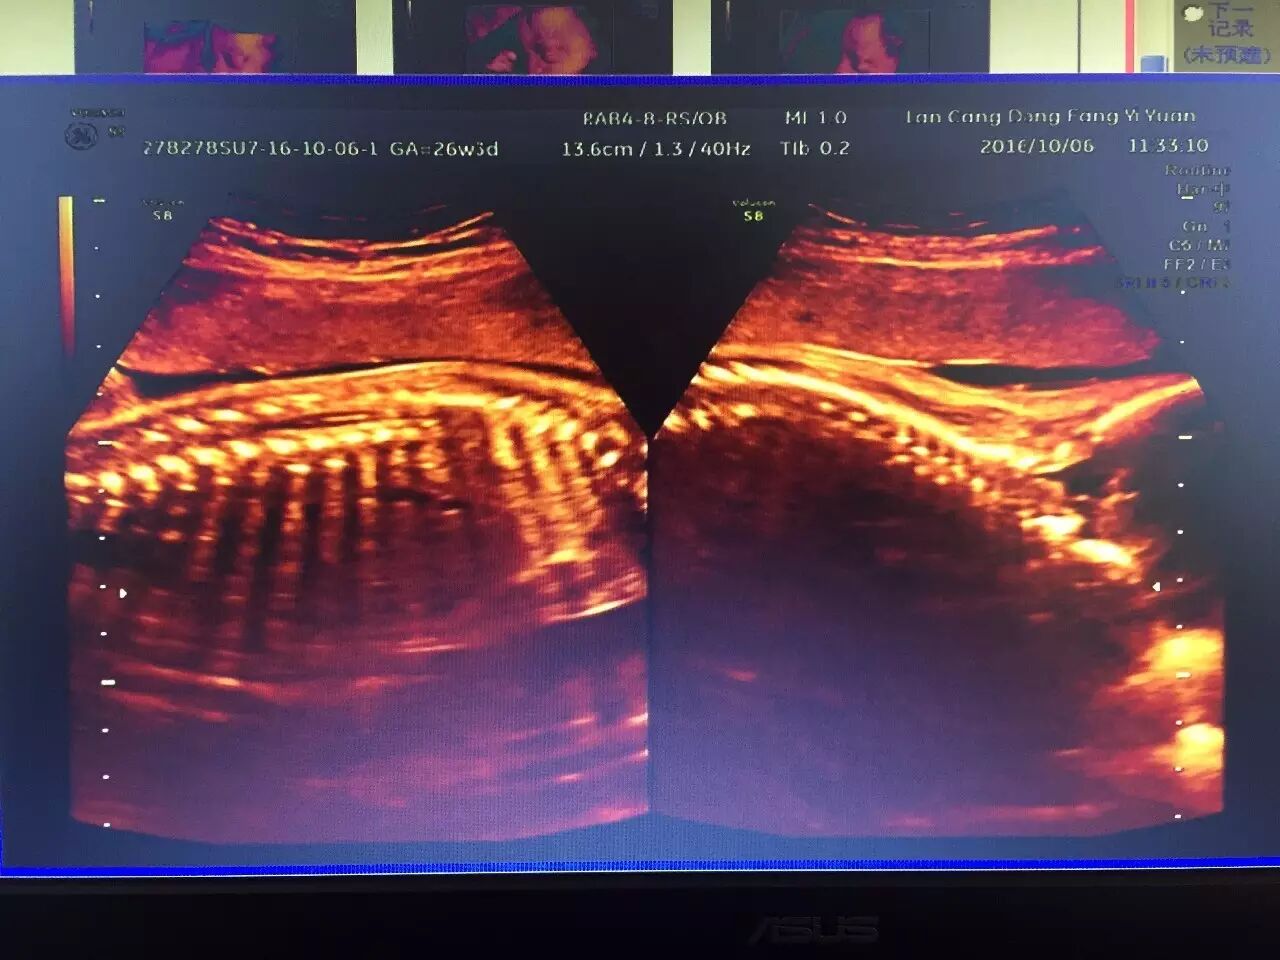

(上图为胎儿脊柱连续完整)